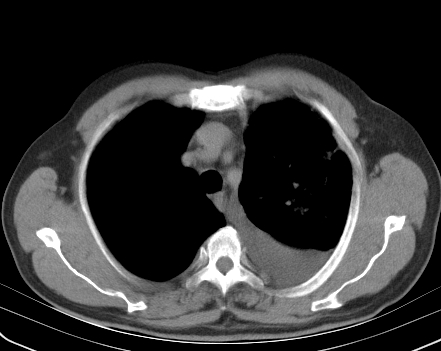

以下是引用老爱克斯新网客在2008-7-31 6:30:00的发言:[br]左肺上叶大片状病灶,左肺上叶支气管狭窄呈鼠尾状,左肺门增大,纵隔内见肿大淋巴结,左侧胸腔积液,余肺清晰。左肺中心型肺癌淋巴结转移,

以下是引用zjb在2008-7-31 6:32:00的发言:[br]左侧中心性肺癌 阻塞性肺炎 肺不张 胸腔积液 建议气管镜

以下是引用zjzjr在2008-7-31 8:45:00的发言:[br]考虑左侧中心性肺癌伴阻塞性肺炎,左肺上叶肺不张,纵隔淋巴结转移;左侧胸腔积液。建议行纤支镜检查。

以下是引用sdzyy在2008-7-31 8:47:00的发言:[br]病灶较治疗前有所进展,胸水增多, 左侧中心性肺癌 并 阻塞性肺炎 肺不张 胸腔积液 可能性大; 建议气管镜检查。 [br] [br]